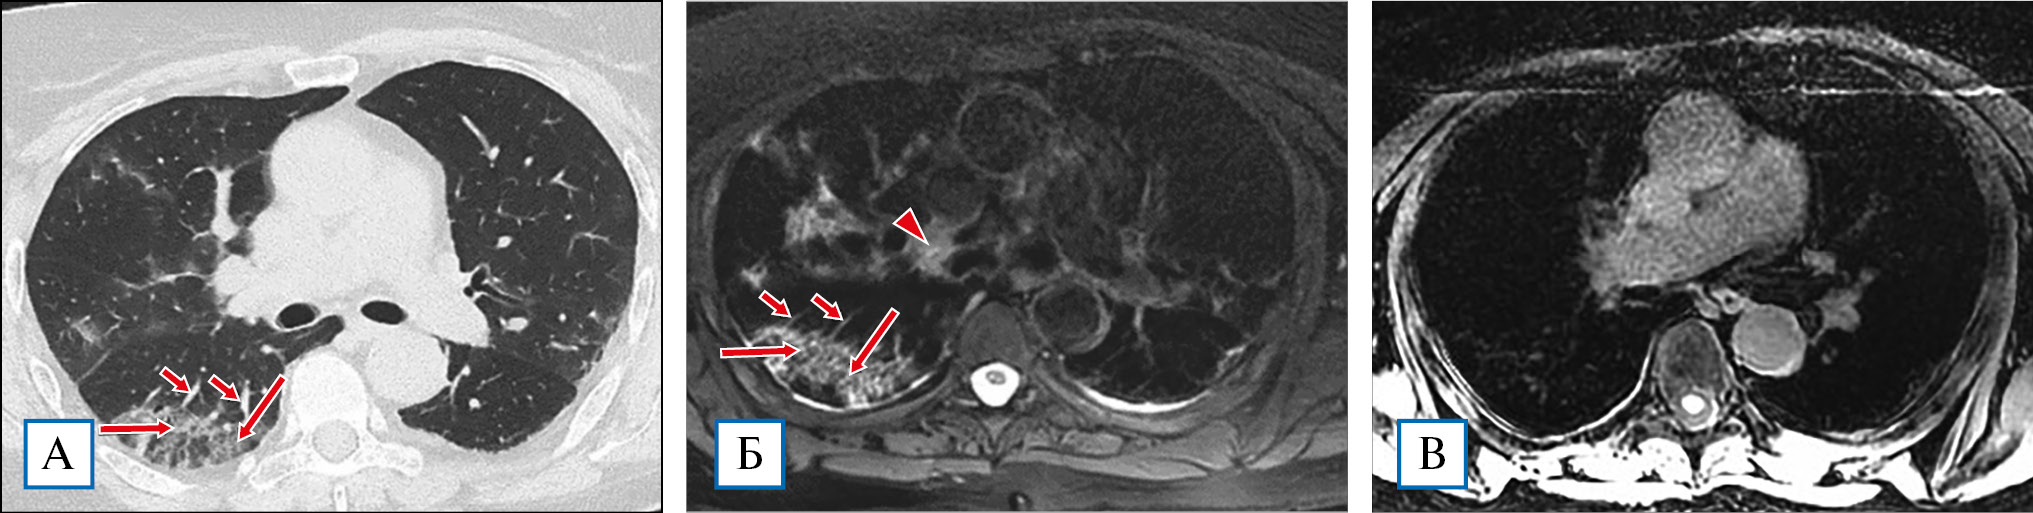

На Т1-ВИ-сканах зоны «матового стекла» либо не визуализировались, либо были представлены меньшими по площади в сравнении с данными КТВР в сопоставимых зонах и определялись как участки незначительного повышения уровня сигнала, хуже отображались также ретикулярные изменения (см. рис. 1). В 11 случаях (73,3%) участки консолидации полностью соответствовали или приближались по характеристикам (размеры, локализация) к изменениям на КТВР, при этом стоит отметить, что выполнение T1-ВИ out phase приводило к более четкому отображению зон консолидации по сравнению с Т1-ВИ in phase (см. рис. 2). Вместе с тем использование Т1-ВИ не позволяет достоверно выявлять изменения интерстиция легочной ткани, в части случаев удается уловить лишь отдельные элементы утолщенных междольковых перегородок или перибронховаскулярного интерстиция, тогда как утолщенные внутридольковые ретикулярные элементы не отображаются вовсе. У 3 пациентов на фоне участков консолидации были зарегистрированы очаги повышенного сигнала на Т1-ВИ с жироподавлением, размерами от 0,4 см до 1,7 см, местами сливного характера, что в сопоставлении с данными Т2-ВИ позволило предположить наличие паренхиматозных кровоизлияний (рис. 5).

Рис. 5. Пациент, 56 лет, тяжелое течение COVID 19. При КТВР констатировано наличие множественных среднего размера зон консолидации в различных сегментах легких, преимущественно перибронховаскулярной и субплевральной локализации (А). При МРТ в нижней доле правого легкого наряду с гиперинтенсивными зонами по Т2 (В, стрелка) выявлялись разнокалиберные очаги повышенного сигнала на Т1-ВИ (Б, стрелки). Обнаруженные изменения расценены как альвеолярные геморрагии